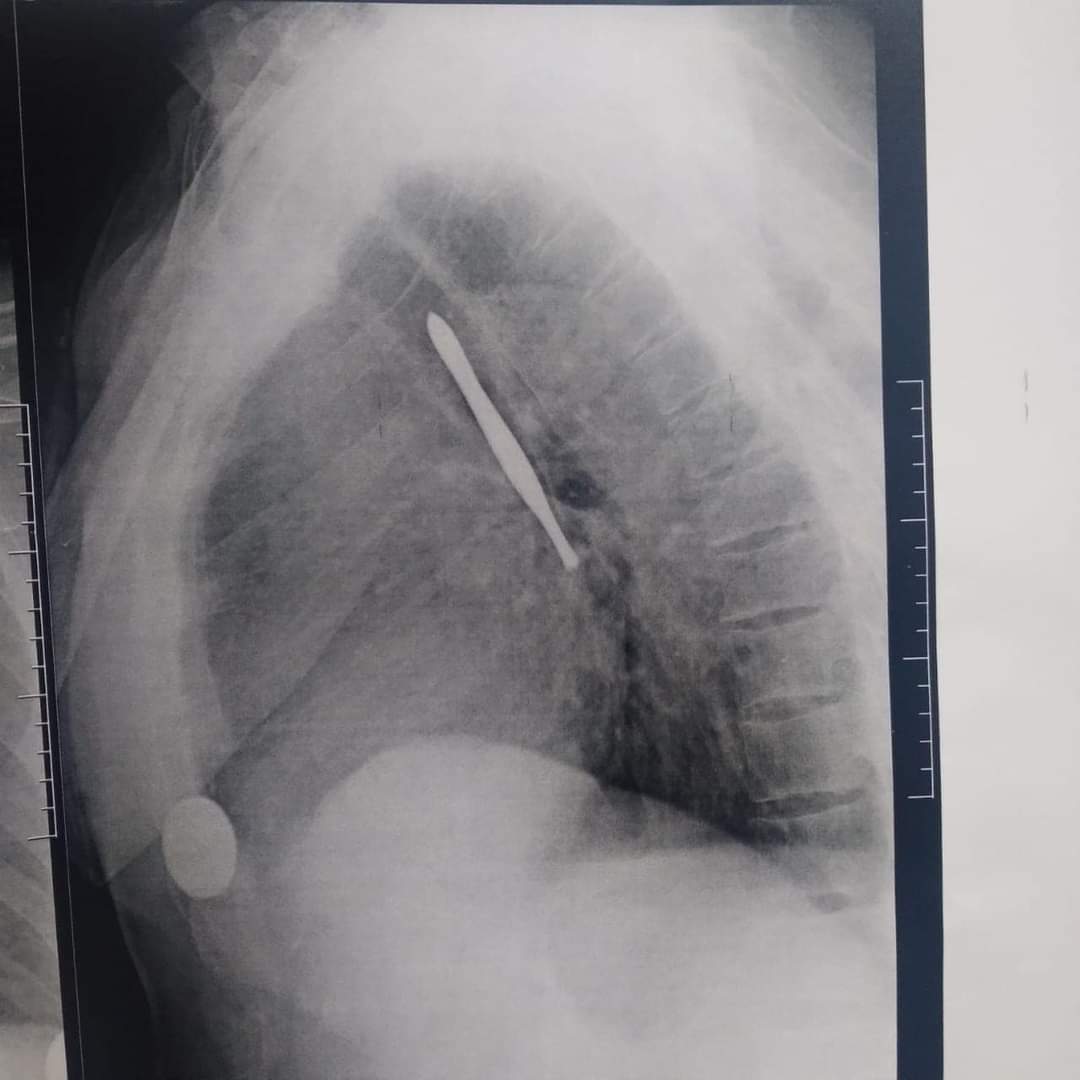

استخراج "ملقاط شعر" من القصبة الهوائية لمريض بمستشفى بنها الجامعي

نجح فريق جراحي بقسم جراحة القلب والصدر بمستشفى بنها الجامعي بمحافظة القليوبية، في استخراج "ملقاط شعر"، من القصبة الهوائية لمريض يعاني من شق حنجري قديم، وأثناء قيامه بتنظيف فتحة الشق الحنجري بطريقة غير طبية وغير صحيحة باستخدام الملقاط ملفوف بمناديل ورقية، سقط منه وابتلعه ودخل لفتحة القصبة الهوائية.

وأوضحت مستشفى بنها الجامعي، فى بيان له، أنه جرى الآن استخراج "ملقاط شعر" من القصبة الهوائية لمريض يعاني من شق حنجري قديم، وبينما يقوم بتنظيف فتحة الشق الحنجري بطريقة غير طبية وغير صحيحة باستخدام ملقاط ملفوف بمناديل ورقية اتشفط منه الملقاط ودخل لفتحة القصبة الهوائية.

وتابعت المستشفى، أنه حضر المريض للقسم في حالة اختناق، وتم دخوله العمليات فورا، حيث نجح الدكتور باسم مفرح الأستاذ المساعد بالقسم، وبمعاونة الدكتور أحمد الخضري مدرس مساعد التخدير، من استخراج "الملقاط"، وخرج المريض بسلامة الله من العمليات ويخضع لاستكمال علاجه بالقسم لحين تماثله الكامل للشفاء.